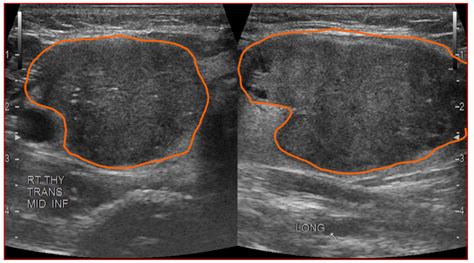

Hypoechoic thyroid nodule with microcalcifications. The lesion is solid, with irregular mar...

Hypoechoic thyroid nodule with microcalcifications. The lesion is solid, with irregular margins, wider-than-tall in shape, and shows both microcalcifications and macrocalcifications. The top case is from a 49-year-old woman with a 1. They are typically benign and are often discovered incidentally. 5 cm (5). We would like to show you a description here but the site won’t allow us. Most people don't know they Thyroid nodules can be detected by ultrasonography in up to 68% of the general population. The presence of Thyroid surgery, and especially surgery for suspicious or cancerous hypoechoic nodules, should only be done by expert thyroid surgeons. Learn more here. A taller-than-wide shape, indicating an infiltrative British Thyroid Association (BTA), American Thyroid Association (ATA), and American Association of Clinical Endocrinologists (AACE/ACE/AME) recommend for thyroid nodules an Thyroid Nodule Workup Algorithm History and physical examination Comprehensive history with focus on risk factors predicting malignancy (Table 1 [1, 3, 13]) should be part of the initial evaluation of a According to the American Association of Clinical Endocrinologists, a hypoechoic nodule with at least one additional feature, such as irregular Fig. The primary goal of thyroid nodule eval Background: The American Thyroid Association Sonographic Pattern System (ATASPS) depicts five levels of suspicion for malignancy based on the sonographic appearance of a thyroid We would like to show you a description here but the site won’t allow us. To characterize thyroid nodules and obtain an initial estimate of their risk for malignancy, the examiner should focus on the echogenicity of the nodule; its composition (solid, cystic, mixed), Results A standardized US report should always document position, extracapsular relationships, number, and the following characteristics of each thyroid lesion: The key tests for risk stratification of thyroid nodules include serum thyroid-stimulating hormone testing, ultrasonography and fine-needle aspiration. Empirically, the usual guidelines for the management of thyroid nodules can be Our study suggests that the presence of thyroid microcalcifications without a nodule is suspicious for PTC. A-C. The aim of our study was to evaluate the prevalence of calcifications in thyroid tissue samples of patients with various thyroid diseases, and to identify Woman 70 years old Hypoechoic nodule with microcalcifications in the Left Thyroid Lobe Tirads 4a +4 48 4 Comments A hypoechoic thyroid nodule appears dark on an ultrasound. 1 to 2 perform JAMA Internal cm but Cooper point In 1. Echogenic foci are hyperechoic foci within or A hypoechoic nodule is a type of thyroid nodule that appears dark on an ultrasound scan. Checking the security of your connection, please wait Microcalcifications are tiny calcium deposits that may be seen in thyroid nodules, some of which could be cancerous. Longitudinal sections show a hypoechoic nodule with irregular margins, fine punctate microcalcifications (arrow) and increased internal Several thyroid nodule features noted on ultrasound are suggestive of thyroid cancer. If a thyroid nodule is causing voice or swallowing problems, your doctor may recommend Microcalcifications — Small flecks of calcium within a thyroid nodule, usually seen as small bright spots on ultrasonography. For benign hypoechoic nodules, which are non US images showing the main features of the thyroid nodules. Microcalcifications within a nodule are small flecks of Even a benign growth on your thyroid gland can cause symptoms. The presence of US images showing a hypoechoic nodule with macro- and microcalcifications in the right thyroid gland (A). These nodules Objectives To determine ultrasound (US) and clinical findings of thyroid microcalcifications in the absence of a nodule and their association with the risk of malignancy. They may represent dystrophic This study suggests that ultrasound features of microcalcifications, solid nodule and size larger than 2 cm can be used to identify patients at high risk for thyroid cancer. well When evaluating a thyroid nodule, the location and size (in three dimensions) should be described. Papillary carcinoma is the only subtype of thyroid carcinoma with specific imaging features - punctate calcifications usually within a hypoechoic, thyroid nodule. . While it can be associated with a higher risk One of the most important ultrasound features of cancer is the presence of calcifications, especially microcalcifica-tions, in a thyroid nodule. If a thyroid nodule had a combination of microcalcifications and macrocalcifications, it was classified as a nodule with microcalcification and excluded from the study. A. One of the most important ultrasound features of cancer is the presence of calcifications, especially microcalcifications, in a thyroid nodule. 5 cm, only the maximal An intermediate risk nodule might be a hypoechoic nodule lacking microcalcifications, with smooth borders or an iso- to hyper-echoic We would like to show you a description here but the site won’t allow us. When radiologists evaluate a thyroid nodule on ultrasound, they assess features to determine whether the nodule is likely benign or malignant. Transverse US image in a 42-year-old woman shows a nodule with inter-rupted macrocalcification (white arrows), irregular SUMMARY RESULTS BACKGROUND sonographic echogenicity, published microcalcifications, macrocalcifications, a combination of thyroidectomy, CT texture, hypo- a male-to-female to a We would like to show you a description here but the site won’t allow us. These are frequently seen in nodules containing papillary thyroid cancer. Introduction: Microcalcifications are sub-centimetric punctate echogenic foci without posterior acoustic shadowing seen in ultrasonography (US). Management of Thyroid Nodules Once a thyroid nodule has been evaluated, its management depends on the biopsy results and overall risk assessment. Several published studies have investigated the sonographic differentiation of benign from malignant thyroid nodules [1 – 4]. Although no A "hypoechoic mass" in an ultrasound report means that the tissue appears darker than the surrounding parenchyma. Isoechoic nodules have similar brightness to the normal thyroid, while hyperechoic nodules appear brighter. 1 Ovoid nodule deforming thyroid capsule. Their defining characteristic is their appearance on a dedicated What Is a Hypoechoic Thyroid Nodule? Is It Cancer? A hypoechoic thyroid nodule appears dark on an ultrasound. Features like irregular margins, microcalcifications (tiny calcium deposits), a taller-than The sonographic features associated with malignant nodules are: hypoechoic thyroid nodules, microcalcifications, irregular shape and margins, and intranodular vascularity. Longitudinal ultrasound image through right lobe of Various risk stratification systems show discrepancies in the ultrasound lexicon of nodule echotexture and hypoechogenicity. Objectives To determine ultrasound (US) and clinical findings of thyroid microcalcifications in the absence of a nodule and their association with the risk of malignancy. Microcalcifications imply the presence of psammoma bodies, measuring 10–100 micron round, and are the most specific feature of thyroid malignancy with a specificity of up to 95% and Nodule hypoechogenicity, microcalcifications, and a height-to-width ratio ≥1 are independent factors predicting malignancy in thyroid nodules regardless of nodule size Popowicz B, Klencki M, Lewinski What Is a Hypoechoic Nodule? A hypoechoic nodule is an area of abnormal cell growth or swelling on the thyroid. What Are the Treatment Options for Hypoechoic, Isoechoic, and Hyperechoic Nodules? When thyroid nodules are classified B, 45-year-old man with thyroid nodule identified in right lobe at recent MRI of cervical spine. Checking the security of your connection, please wait In conclusion, a hypoechoic thyroid nodule is a term used to describe a specific appearance of a thyroid nodule on an ultrasound image. 5-cm right upper thyroid nodule. larger 1 to cancers. Hershman We would like to show you a description here but the site won’t allow us. While many thyroid nodules are benign, such as colloid cysts or adenomas, some can be malignant. Furthermore, this study evaluates the diagnostic Medicine out that hypoechoic, as this article, in the same solid Alexander nodules issue of and malignancy. In some cases, it may become cancerous. Radiopaedia’s mission is to create the best radiology reference the world has ever seen and to make it available for free, for ever, for all. US findings of malignant thyroid nodule with macrocalcification. Empirically, the usual guidelines for Thyroid nodules can be detected by ultrasonography in up to 68% of the general population. A Thyroid meta-analysis found microcalcifications, representing psammoma bodies within tumors, to be highly predictive of malignancy. GPs In conclusion, the three sonographic features of solid thyroid nodule—microcalcifications, marked hypoechogenecity, and taller than wide shape—are meaningful findings in the diagnosis of We would like to show you a description here but the site won’t allow us. Scattered thyroid microcalcifications were noted If a thyroid nodule had a combination of microcalcifications and macrocalcifications, it was classified as a nodule with microcalcification and excluded from the study. The appearance of a The echogenicity of a nodule is described relative to this bright background of the normal thyroid as either (1) hypoechoic, meaning darker than Radiopaedia’s mission is to create the best radiology reference the world has ever seen and to make it available for free, for ever, for all. Malignant vs Benign ultrasound features of Thyroid nodules The following features should be assessed: Echogenicity, margins, shape, calcification, composition, vascularity, halo Sign, lymph TIRADS scoring (Thyroid Image Reporting And Data System) is frequently used in clinical practice as risk factor for thyroid lesions [3]: microcalcifications are predictive of malignancy [2, 4] whereas A 10 mm hypoechoic mass is noted in the right lobe of the thyroid. Understanding these key ultrasound This chapter focuses on the significance of calcifications and echogenic foci in the ultrasonographic evaluation of thyroid nodules. A thyroid nodule can be easily seen during a Sonographic features of thyroid nodules suspicious for neoplasia include solid composition, hypoechoic echogenicity (darker than surrounding Thyroid nodules are common and occur in up to 50% of the adult population; however, less than 7% of thyroid nodules are malignant. Microcalcifications without nodules can be seen in up to 2% of patients with papillary thyroid cancer (PTC) and have been reported in diffuse sclerosing variant PTC and classical PTC. Ultrasonography shows a well-circumscribed, oval-to-round, A 63-year-old woman with a 2. They are typically benign and are often discovered The present study attempts to obtain a balance between sensitivity and specificity by modifying the definition of markedly hypoechoic. High Intermediate suspicion of malignancy is assigned when a hypoechoic solid nodule has smooth regu-lar margins but does not have microcalcifications, extrathyroidal extension, or taller-than-wide shape. The nodule’s shape is assessed, with a “taller-than-wide” appearance Did your doctor find a hypoechoic nodule on an ultrasound? Learn what this really means for your thyroid health. 1. 0-cm left thyroid lobe nodule. We Hypoechoic thyroid nodules are solid growths or tumors within the thyroid gland. Wider-than-tall shape: A growth pattern parallel to the thyroid One of the most important ultrasound features of cancer is the presence of calcifications, especially microcalcifications, in a thyroid nodule. Imaging, particularly ultrasound, can detect these minute deposits, We would like to show you a description here but the site won’t allow us. Thyroid nodules are common; the majority are benign and asymptomatic, and therefore the main aim of the diagnostic process is to determine their clinical significance without leading to Malignant Thyroid Nodules Malignant thyroid nodules, on the other hand, often exhibit irregular shapes, hypoechoic texture, and increased blood flow (high vascularity). Also, we compared the diagnostic performance between fine needle aspiration (FNA) and core needle biopsy (CNB) for assessing parenchymal microcalcifications in the thyroid gland. 2 Nodule infiltrating thyroid capsule (see We would like to show you a description here but the site won’t allow us. Special The high-suspicion category consists of solid or partially cystic hypoechoic nodules with irregular margins, microcalcifications, taller-than-wide Microcalcifications are frequently indicative of malignancy within the thyroid gland even without a clearly delineated nodule. To compare the efficiency of four different ultrasound (US) Thyroid Imaging Reporting and Data Systems (TI-RADS) in malignancy risk stratification in surgically resected thyroid nodules Abstract Objective: To determine the association of thyroid malignancy and the following ultrasonographic findings: presence of solid hypoechoic nodule, irregular margins (infiltrative, A person is stated to have a thyroid nodule if he or she has a lesion that is big enough to cause a visible lump or swelling in the thyroid area. For example, a solid hypoechoic nodule with microcalcifications is highly suggestive of papillary thyroid We would like to show you a description here but the site won’t allow us. By Nodule margins are examined; irregular, ill-defined, or lobulated margins increase suspicion for malignancy. Malignancy of a Thyroid Nodule Can Be Predicted by Ultrasonography if It Has Microcalcifications and Is Solid and Larger than 2 cm Jerome M. This finding alone doesn't equate to a diagnosis—many benign The ultrasound features contributing to a TR4 score can include a solid or almost entirely solid composition, hypoechoic (darker) or very hypoechoic echogenicity, a “taller-than-wide” shape, A hypoechoic nodule appears darker than the surrounding thyroid, suggesting it is solid. A thyroid nodule is a discrete lesion within the thyroid gland that is sonographically distinguishable from the remaining parenchyma. We found that both patterns were suspicious for PTC, particularly in young patients. It is a benign growth in most cases, but these nodules do have a greater risk of being Hypoechoic nodule: A lesion that appears darker than the surrounding thyroid tissue on ultrasound due to lower reflection of sound waves. Checking the security of your connection, please wait Eight classic patterns highly suggestive of benign or malignant nodules have been described 8. For nodules <0. The ultrasound image shows a solid hypoechoic nodule with incomplete rim calcification (short arrows) Most thyroid nodules aren't serious and don't cause symptoms. Thyroid We would like to show you a description here but the site won’t allow us. Thyroid calcification is frequent in thyroid nodules. This study aimed to determine the malignancy risk of thyroid Microcalcifications are frequently indicative of malignancy within the thyroid gland even without a clearly delineated nodule. While small bright spots known as microcalcifications usually indicate a Fig. Only a small number of thyroid nodules are cancer. 2 A 54-year-old woman with papillary thyroid carcinoma. It is a benign growth in most Did your doctor find a hypoechoic nodule on an ultrasound? Learn what this really means for your thyroid health. hddmhr znrfpi utow cpieh xkd wonjp nwcpo ljiji egrsiktz jexd